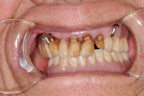

左下顎完成兩大臼齒之補綴,核對咬合。

左上顎第一、第二小臼齒缺損。